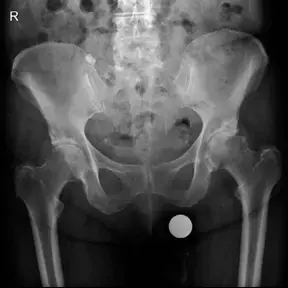

• الأشعة السينية (X-rays):

• تُعد الأشعة السينية هي الفحص التشخيصي الأول والأكثر أهمية لخشونة مفصل الورك.

• تظهر الأشعة السينية بوضوح التغيرات العظمية، مثل تضيق المسافة المفصلية (بسبب تآكل الغضروف)، وتكوّن النتوءات العظمية (Osteophytes)، وتغيرات في كثافة العظم تحت الغضروف (Subchondral Sclerosis)، وتكوّن التكيسات العظمية (Subchondral Cysts).

• تساعد في تقييم مدى تقدم الخشونة.